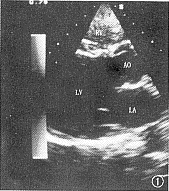

1.超声心动图在左室长轴切面显示:右室心腔内径变小,纵径多在1.8~2.0 cm,其中2例三尖瓣环小,三尖瓣活动欠佳,1例三尖瓣疑为闭锁。心尖四腔切面显示:房间隔中部回声中断,长径达1.0~2.5 cm。大动脉短轴切面显示:大动脉关系和肺动脉正常(图1,2)。

图1,2 超声心动图。RV=右室;RVOT=右室流出道;PA=肺动脉;AO=主动脉;RA=右房;LA=左房;ASD=房间隔缺损。图1为左室长轴切面,显示右室心腔小,纵径为1.8 cm。图2为大动脉短轴切面,显示右室漏斗部、肺动脉及三尖瓣大小正常,房间隔回声中断